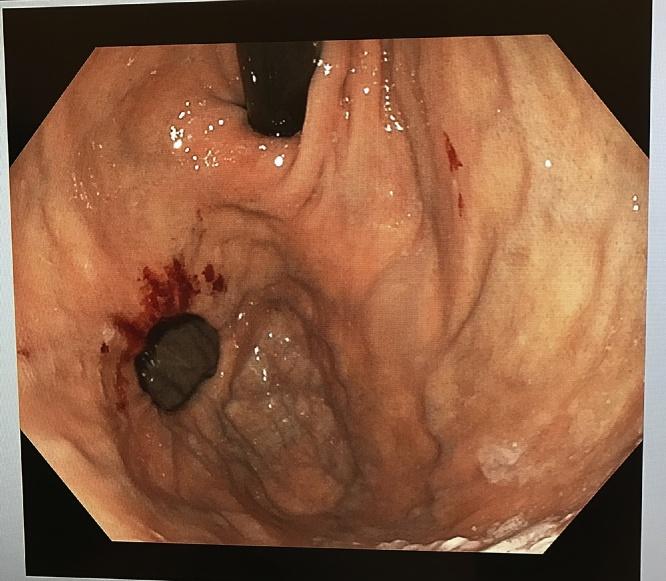

CASE PRESENTATION

A 77-year-old gentleman presented to the outpatient clinic with a one-month history of passing black stools. He was arranged for an oesophagogastroduodenoscopy (OGD) which revealed a gastric body polyp and a diverticulum in the fundus of the stomach.

一名77岁男性到门诊就诊,有一个月排黑便病史。他接受了食管胃十二指肠镜检查(OGD),结果显示胃体部有息肉,胃底部有一个憩室。